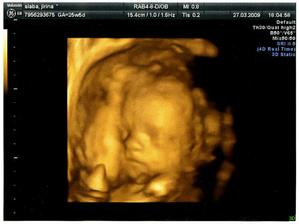

Ve 20tt nám velký ultrazvuk potvrdil, že to bude chlapeček. Hned bylo jasné, že se bude jmenovat Vojtíšek 🙂